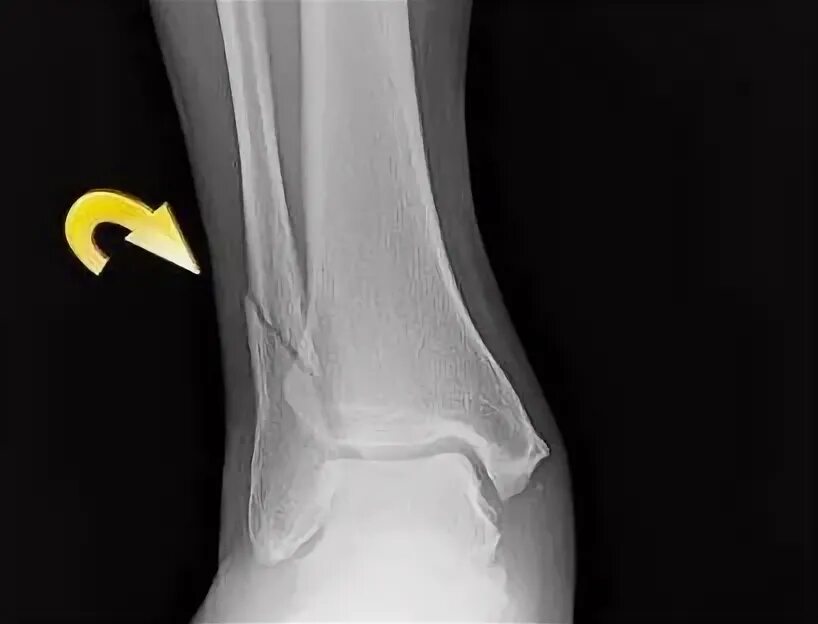

Перелом 3 берцовой кости